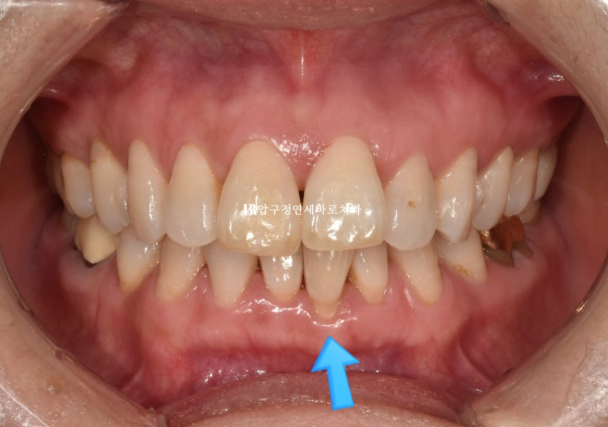

파란 화살표 부분은 잇몸이 주변치아에 비하여 내려가 있습니다.

그 이유는 배열에서 가장 벗어난 치아여서 입니다.

제자리로 넣어주면 잇몸이 회복되기도 합니다.

위 앞니 두개가 튀어나와있고 회전이 되어있습니다.